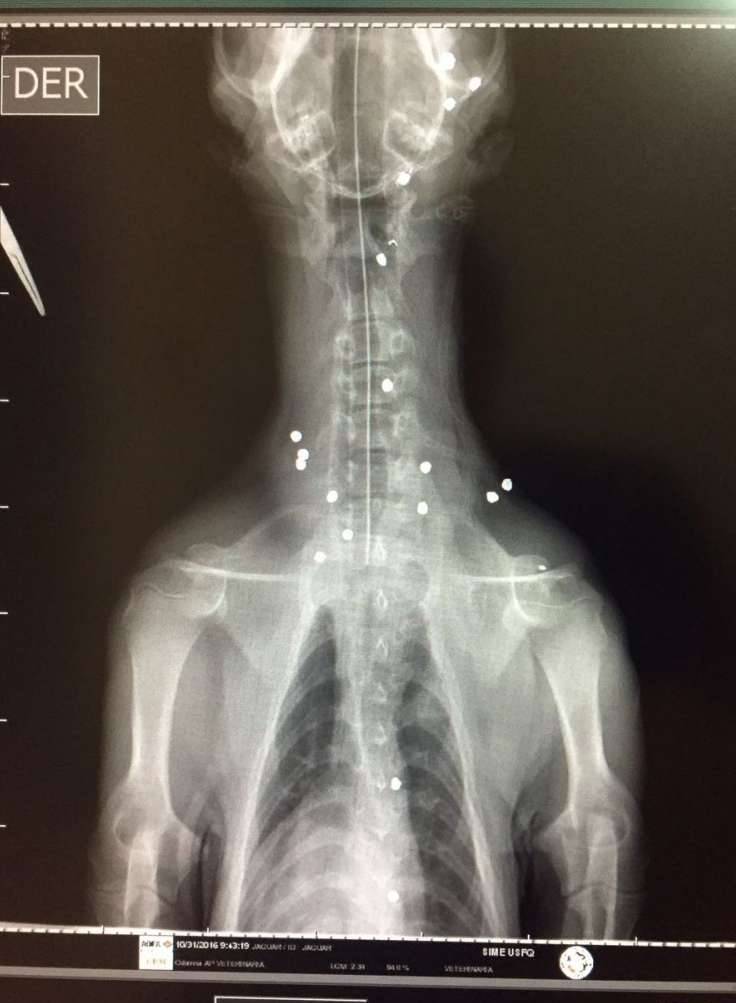

▼动物医院的兽医表示,这年纪的美洲豹本应属于活泼好动的,这头美洲豹却全身瘫软无力,但因为没有明显的外伤,所以决定用X光来诊断,结果发现牠体内竟有18颗子弹,不得不紧急进行手术。

▼在牠体内的18颗子弹中,其中两颗甚至伤及脊椎,情况令人担忧。